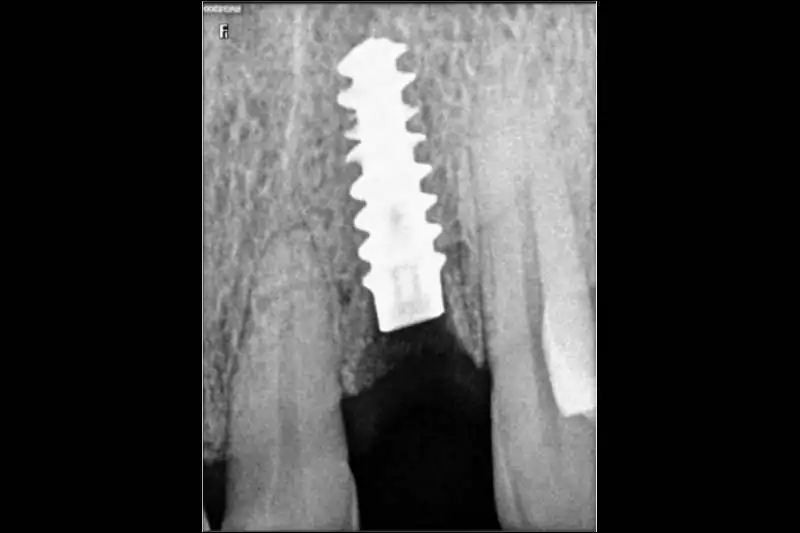

After a thorough clinical examination of your jaw bone, the Best dentist in Pune at Smilex confirms the available jaw bone by CBCT scan or X-rays. The doctors then administer a very small cut in the gums under local anesthesia. A painless drill sequence leads to the final drill position, after which the dental implants in Pune are placed in the bone. Gums are then placed back in their original position. A single implant procedure takes up to 45 mins to be done.